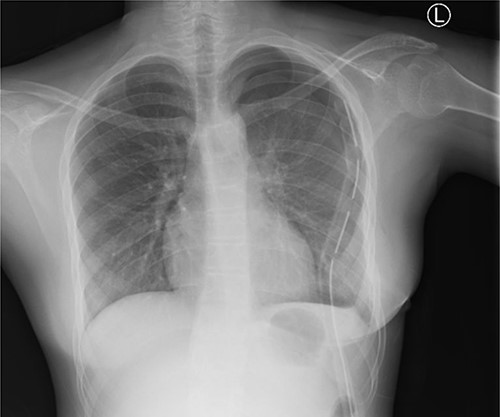

Chest X-ray (PA) shows no mass in the left hemithorax after thoracotomy and tumor resection; chest tube in situ; heart and lungs appear normal.